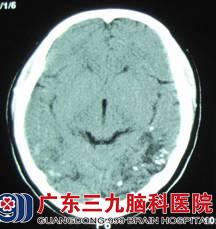

小邓,19岁,右手发作性抽搐已有15年,通过检查,CT及MRI的结果提示:右侧顶叶深部白质内病灶,血清裂头蚴抗体呈阳性。神经外六科的吴杰主任诊断为:1、症状性癫痫,2、右侧顶叶中央区脑裂头蚴病。

术前颅内影像